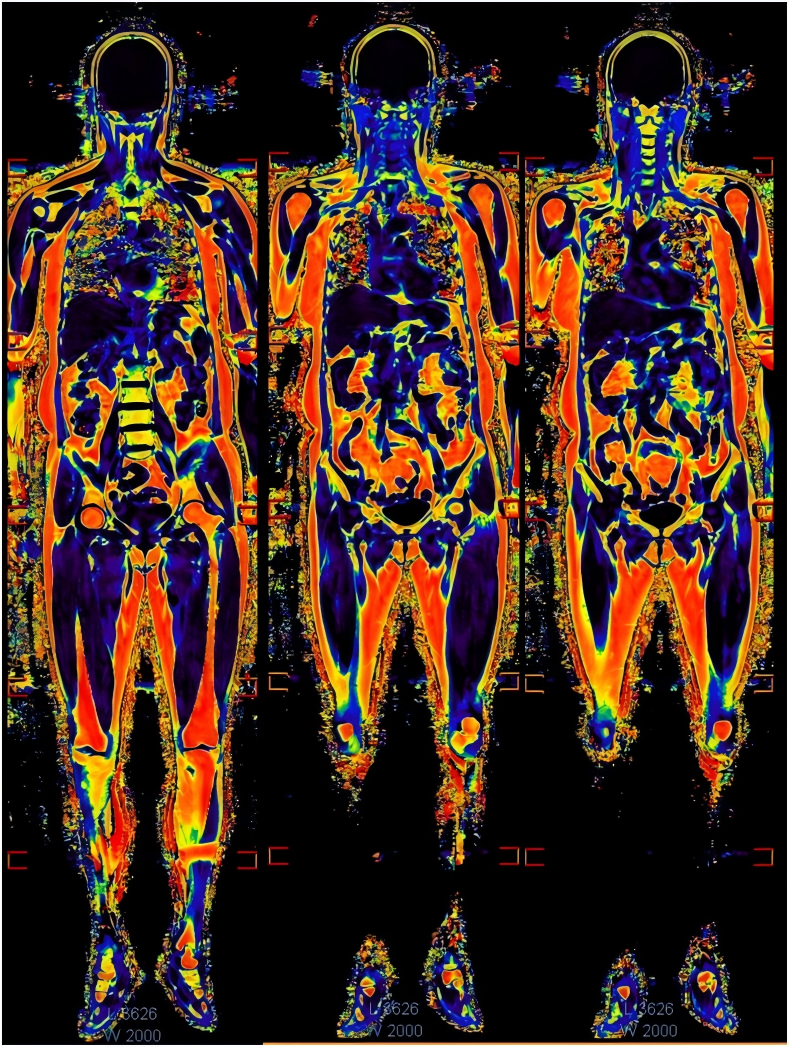

另将这个序列改为冠状位扫描,采用多段扫描拼接,最后得到全身的脂肪含量分数图。

由于mDIXON Quant序列本身扫描时间就非常短。完全全肝采集仅仅需要15秒。全身扫描,每一段也仅仅需要15秒左右,6段扫描完,裸时间是90秒,再加上移床时间,3分钟能完成全身脂肪定量扫描。